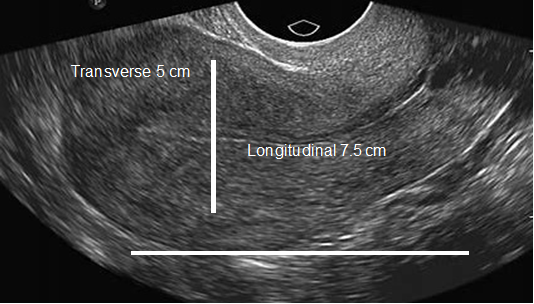

In patients without endometriosis, the average longitudinal measurement of the uterus was 7.5cm with a range of 5cm to 8.5cm and the average transverse measurement was 5.0cm with a range of 4.5cm-6.4cm (Figure 1).26 In the presence of endometriosis, this size increased depending on the size and site of the endometrioma. The Figure 2 shows dilation of the uterine cavity due to the presence of endometrioma. In this patient, the transverse measurement increased to 6.5cm (Figures 3a & 3b).

Figure 1 An ultrasound image of the uterus showing normal size. The horizontal line shows longitudinal measurement (7.5 cm), and the vertical line shows transverse measurement (5 cm).